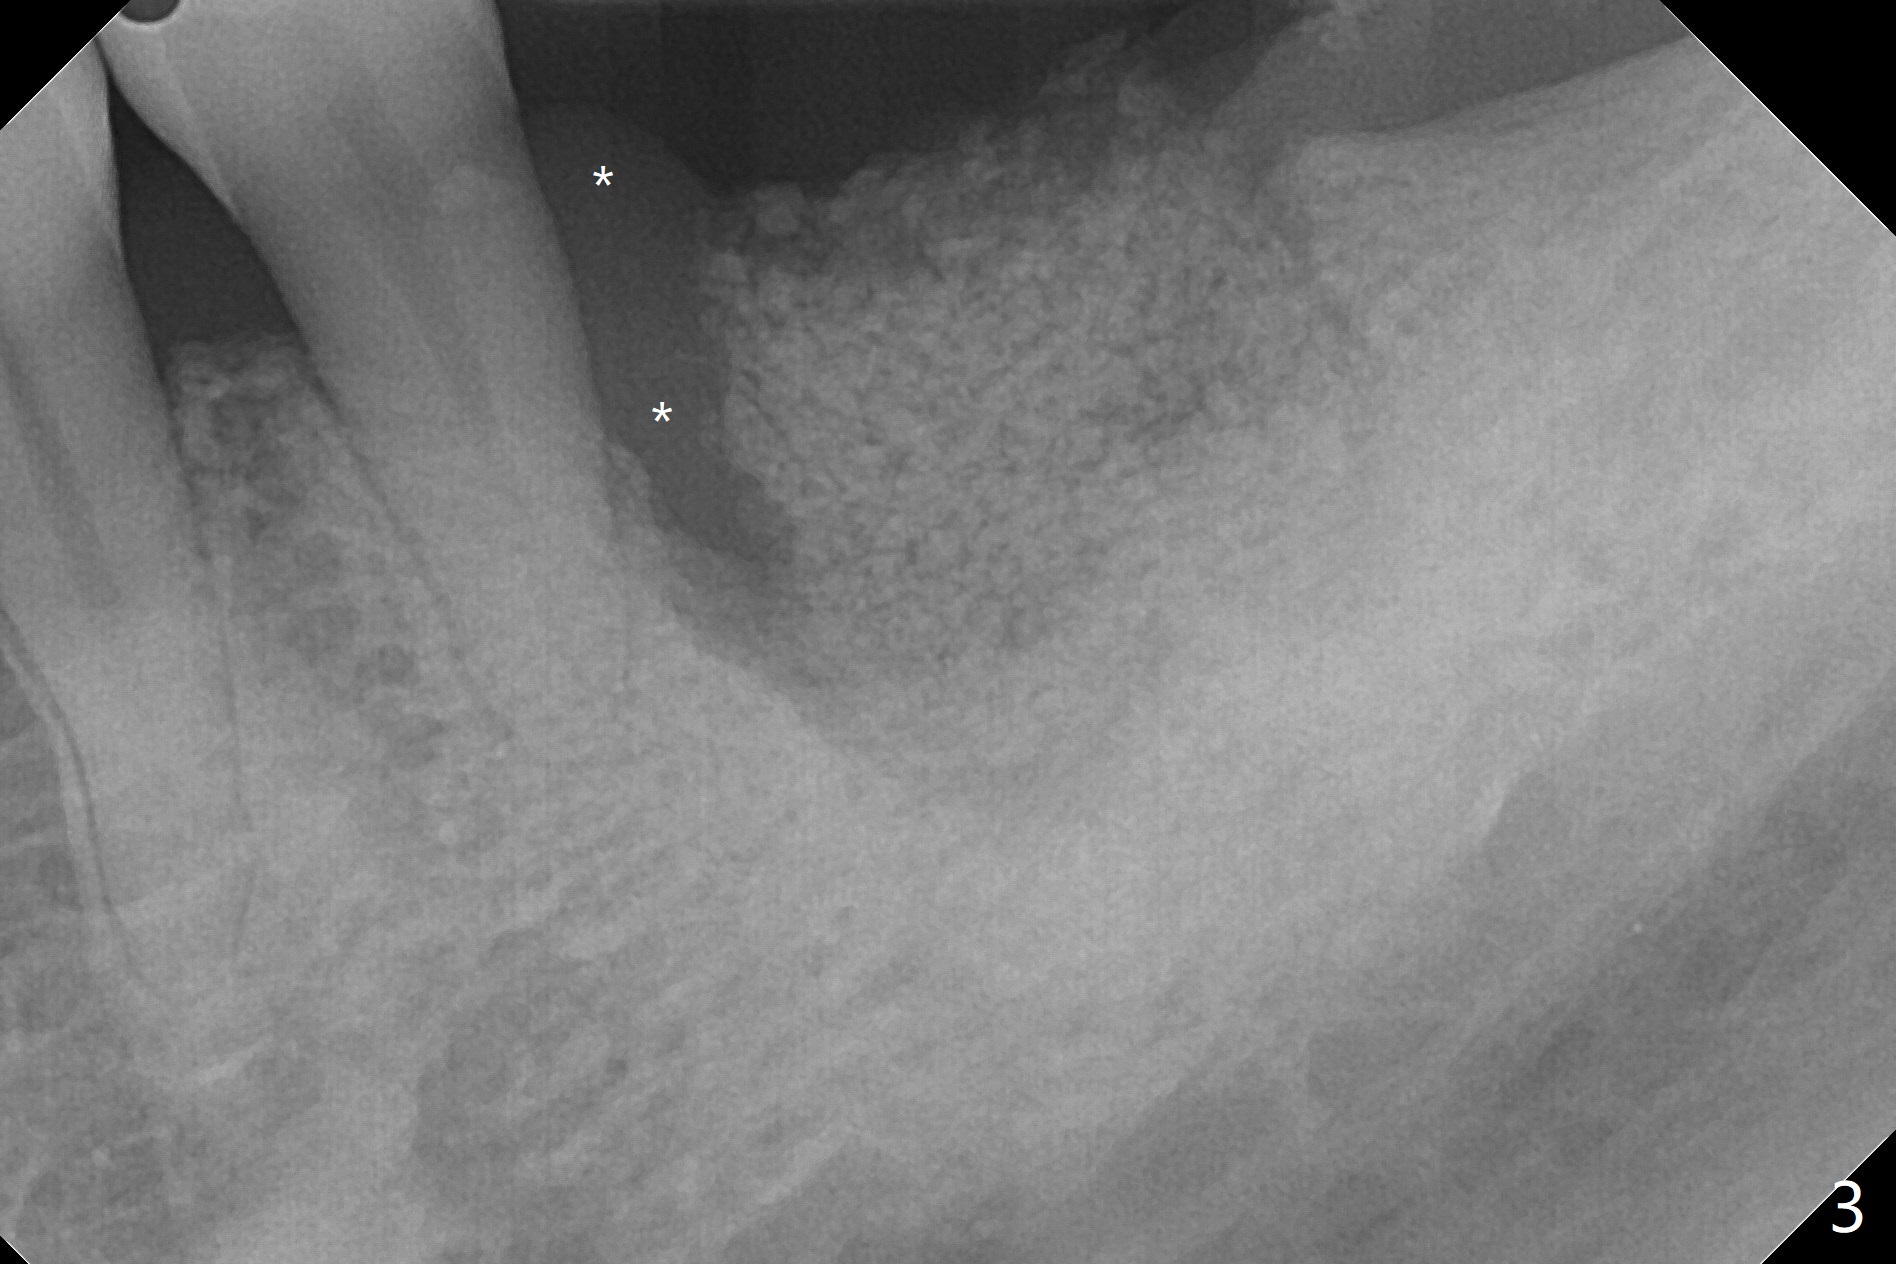

A 50-year-old man (smoker, bruxer (also missing the tooth #2 and 3)) requests extraction of the tooth #19 with mobility and buccal gingival infection (Fig.1 *). There is severe bone loss around the mesial root (Fig.2 M). It appears that the soft tissue (Fig.3 *) prevents the bone graft from being deposited in the distal surface of the neighboring root.